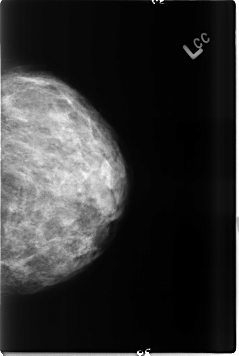

B_3485_1.LEFT_CC

LEFT_CC LINES 4616 PIXELS_PER_LINE 3096 BITS_PER_PIXEL 12 RESOLUTION 50 NON_OVERLAY